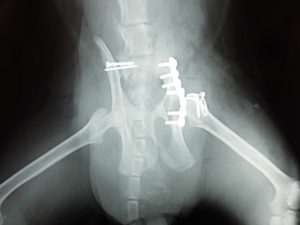

猫の骨盤骨折

2015.12.08